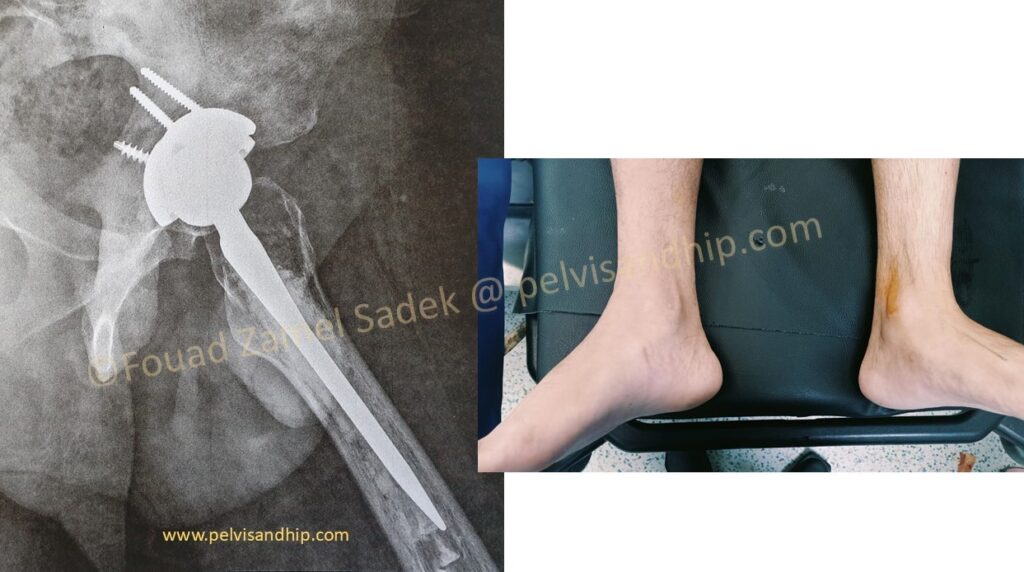

The obvious leg length discrepancy on the left side. The scar of previous interventions suggest some lateral based surgical approach which is well healed with no obvious suspicion of active inflammation.

Through a posterior approach, the true acetabulum was identified and cleared of all haling tissues and debris. Radical releases including the postero superior as well as the inferior capsules were done. A periacetabular release procedure was carried out with additional releases of the gluteal maximus attachment into the gluteal tuberosity of the femur. A superior trabecular metal augment was applied as per routine. A porous coated cementless spherical cup was inserted close to the TAL. No further grafting was needed.

A cemented stem was chosen due to very poor quality bone withing the metaphysis of the femur and for that a cemented option for the femoral stem was chosen. The leg length adjusted as per immediate postoperative finding. At the last follow up, patient is walking with no support. He has a very reasonable abduction function. He has returned to work with good satisfaction. Still working on improving his abduction function.